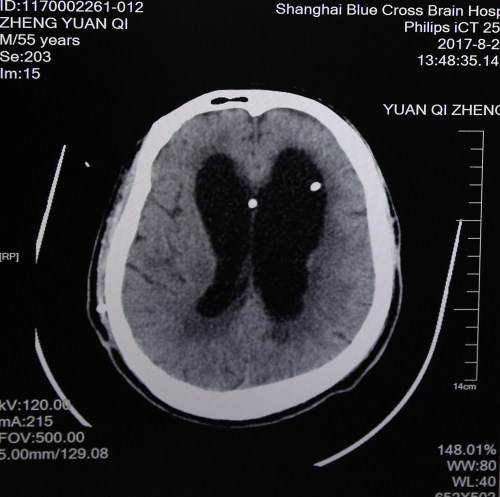

最近头颅CT影像:脑沟回明显,脑室缩小,脑压降低,重新置管分流后有效

但郑元齐每天傍晚会发烧,经会诊查到之前置入的脑室-腹腔分流管腹腔段阻塞、腹壁出现化脓,脑脊液混浊,肺部感染,而且有低压性脑积水,情况不乐观,随即决定重新置管,转入神经外科。5月8日,神经外科主任医师、博士研究生导师、沈建康教授亲自为郑元齐撤出原来的分流管,安置omaya囊,每日引出感染的脑脊液,5月30日脑脊液完全正常后又为郑元齐重新分流。术后,郑元齐颅内感染、反复高热等情况明显好转。

8月8日,郑元齐出现低血压,癫痫大发作,情况十分危急,被紧急送进ICU病房进行抢救后病情平稳。ICU治疗以充分氧合、消除炎症和促醒为主,ICU副主任医师李鲁萍给予纤支镜灌洗治疗控肺吸痰,邀请中医科给予针灸刺激头皮神经末梢促醒,中药活血化瘀等中西医结合治疗,且严密监控病情病症变化。此后,郑元齐反复高热、癫痫、低氧等症状没有再出现,肺部感染得到进一步控制,痛觉越来越敏感,情况一天天好转。